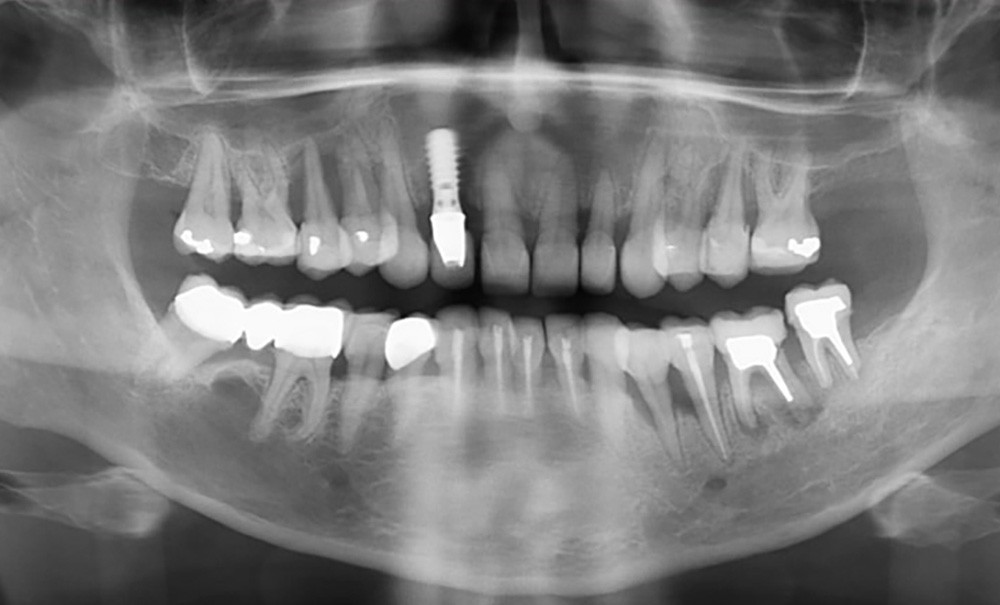

Le diabète est considéré comme un facteur de risque majeur des parodontites. Parallèlement, la maladie parodontale est considérée comme la 6e complication du diabète. En effet, le diabète contribue à l’initiation ou à l’amplification de l’inflammation et de la destruction des tissus parodontaux. Un lien bidirectionnel entre ces deux maladies est communément admis et a été établi depuis de nombreuses années. De plus, il est démontré que l’amélioration des paramètres cliniques de l’une d’elles contribue à l’amélioration de la seconde. Ainsi, afin de favoriser la prise en charge globale des patients diabétiques et de prévenir les complications systémiques liées au diabète, le chirurgien-dentiste doit mener une anamnèse rigoureuse, un examen clinique précis et complet, ainsi que, si nécessaire, un traitement parodontal adapté.